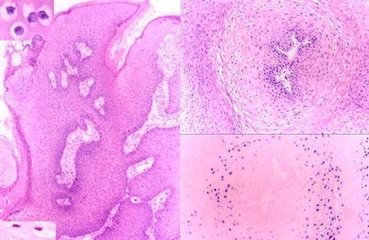

尖锐湿疣:尖锐湿疣又称生殖器疣或性病疣,是由某些类型的人类乳头瘤病毒(HPV,其中HPV6、11型占总数90%)引起的增生性疾病,潜伏期在3个月左右,短者3周,长者8个月以上,平均为3个月,患者主要是性活跃人群,以20~30岁为发病高锋。发病很大程度上取决于接种的病毒数量和机体特异性免疫力。临床上表现为尖刺状,表面潮湿,故而得名。临床上可分为:男性尖锐湿疣、女性尖锐湿疣、儿童尖锐湿疣。尖锐湿疣可发展成巨大疣,反复发作,造成患者思想负担。